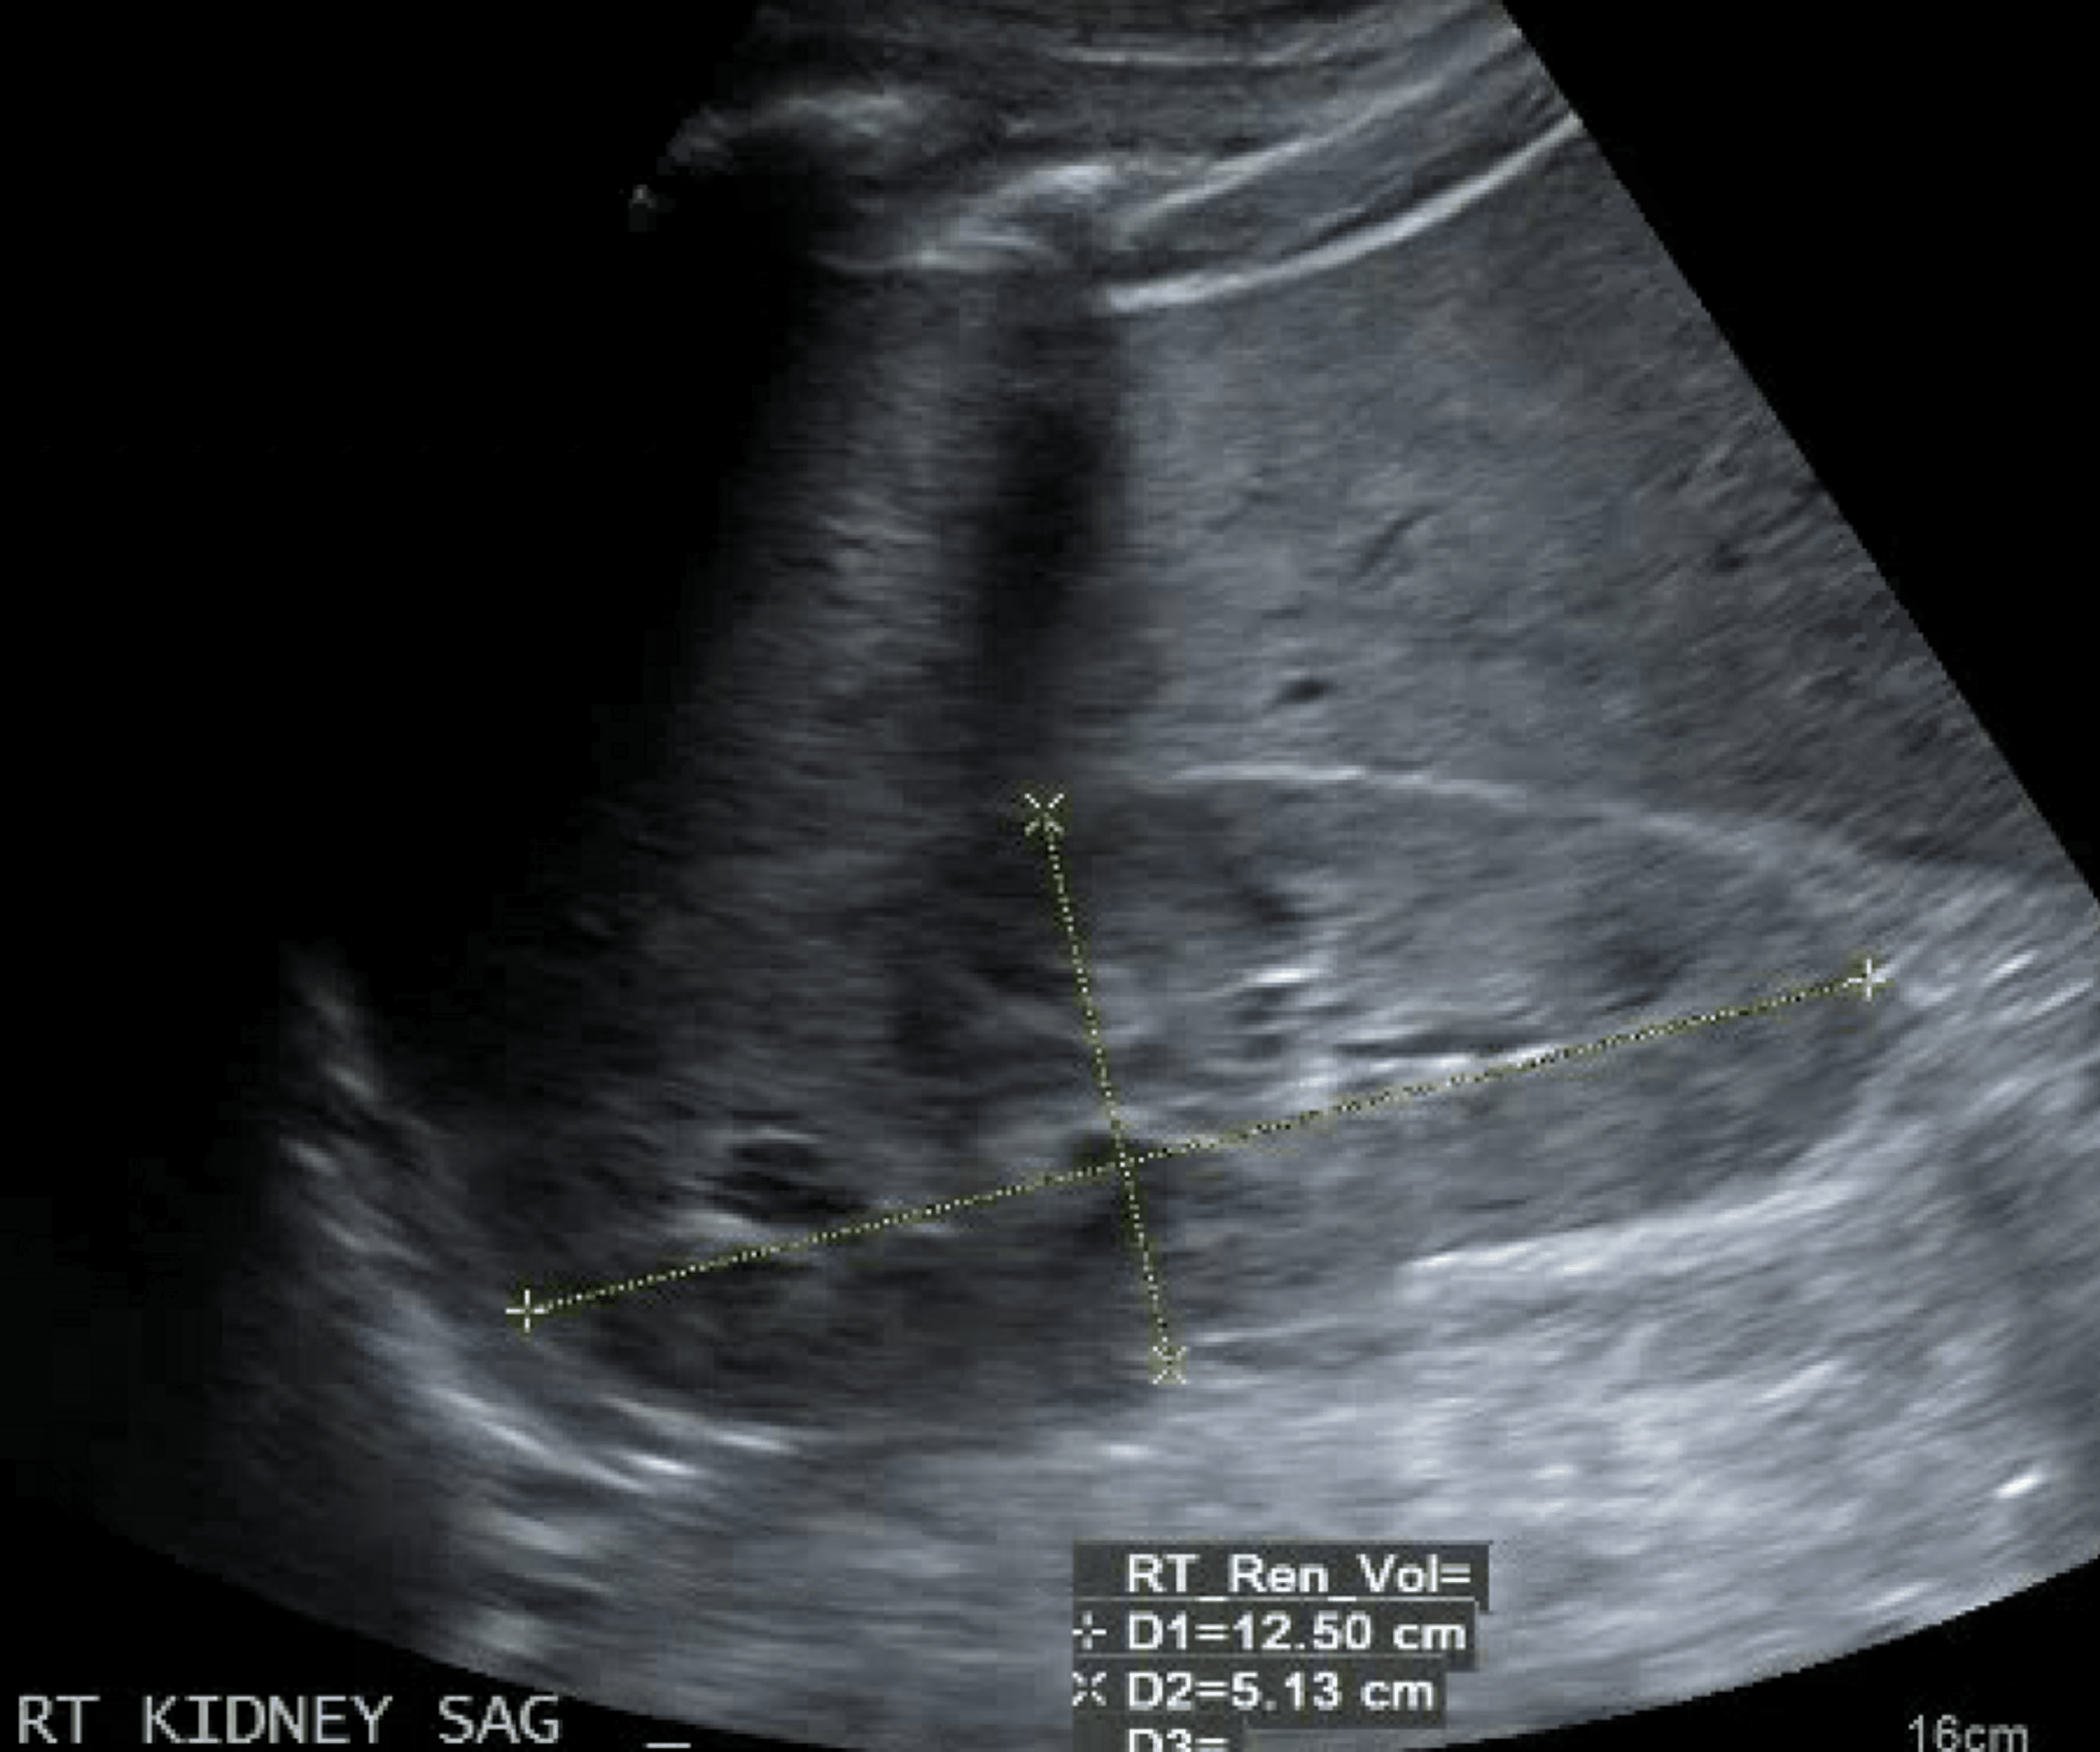

Kidney ultrasound in a patient with TBMD, proteinuria and CKD, showing Proteinuria Renal Ultrasound Determination of size and localization of the kidneys, abdominal pain, flank pain, hematuria, proteinuria,. The presence of proteinuria is an independent risk factor. indications include (but are not limited to): It may accompany chronic diseases, but can also be the first sign of. proteinuria is a common finding in adults in primary care practice. persistent proteinuria is. Proteinuria Renal Ultrasound.